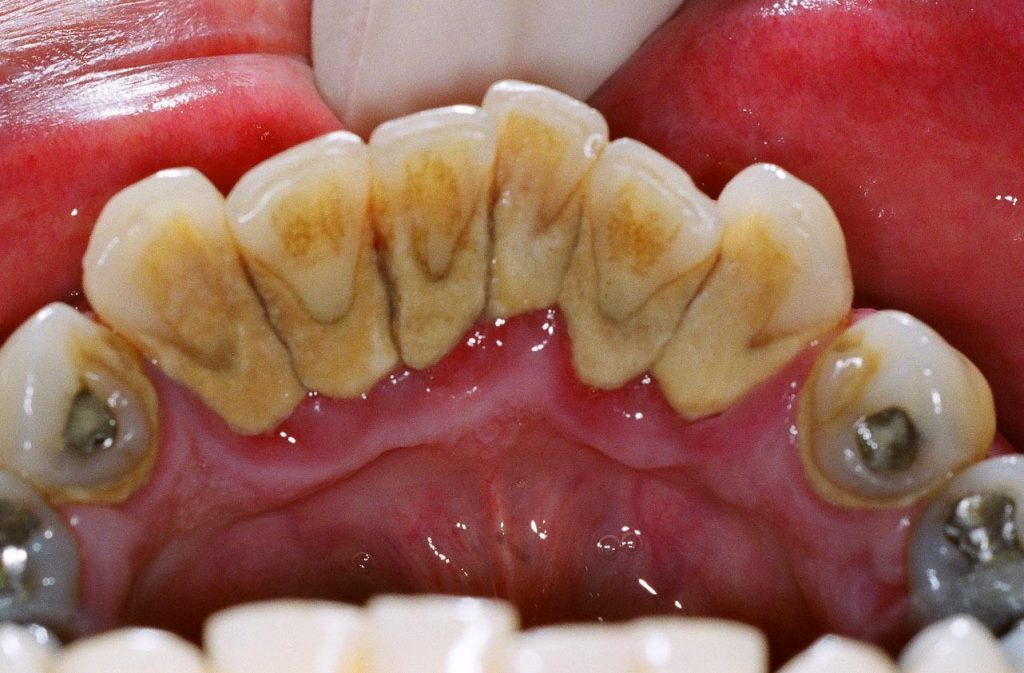

12 Diagnosis and Management of Dental Caries Pocket Dentistry Light Therapy For Dental Caries Pointed out that photodynamic therapy combined with 405. in this review article, we aimed to review the studies associated with the application of photodynamic therapy. hwang et al. Pointed out that photodynamic therapy combined with 405 nm light source and chlorella natural. hwang et al. photodynamic therapy studies have shown promising results for inactivation of microorganisms. Light Therapy For Dental Caries.